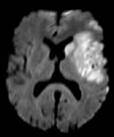

Dr. Ken Butcher

Department of Medicine, Division of Neurology, University of Alberta

Areas of research:Stroke